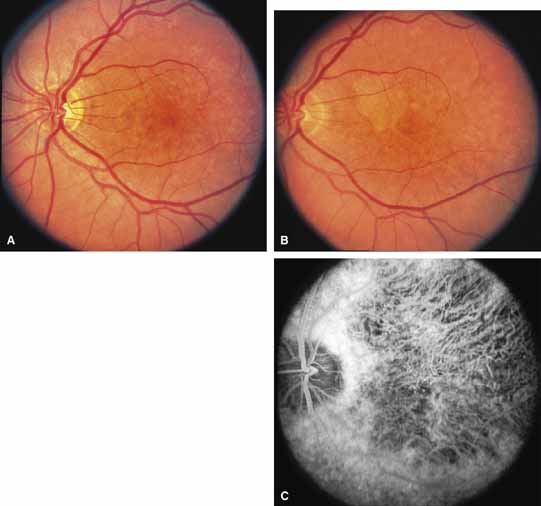

Bietti's crystalline dystrophy (MIM No. 210370) of the cornea and retina is an autosomal recessive disorder that is characterized by the presence of crystals of unknown composition in the stroma of the peripheral cornea and at several layers of the retina (Figs. 3A and 3B).23 The disease can be subdivided into regional and diffuse forms, and the lack of any reports of the two patterns in the same family suggests genetic heterogeneity and not just variable expressivity.24,25 The regional form begins in midlife as pericentral scotomas that cause difficulty reading and reduced central visual acuity. Peripheral retinal function is retained and the electroretinogram and electrooculogram are normal or near normal even in moderately advanced disease. The fundus appearance and fluorescein angiogram reveal regional loss of pigment epithelium and choriocapillaris limited to the posterior pole (Figs. 3C and 3D). The finding of abnormal crystals in leukocytes indicates that this is a systemic metabolic disorder.24